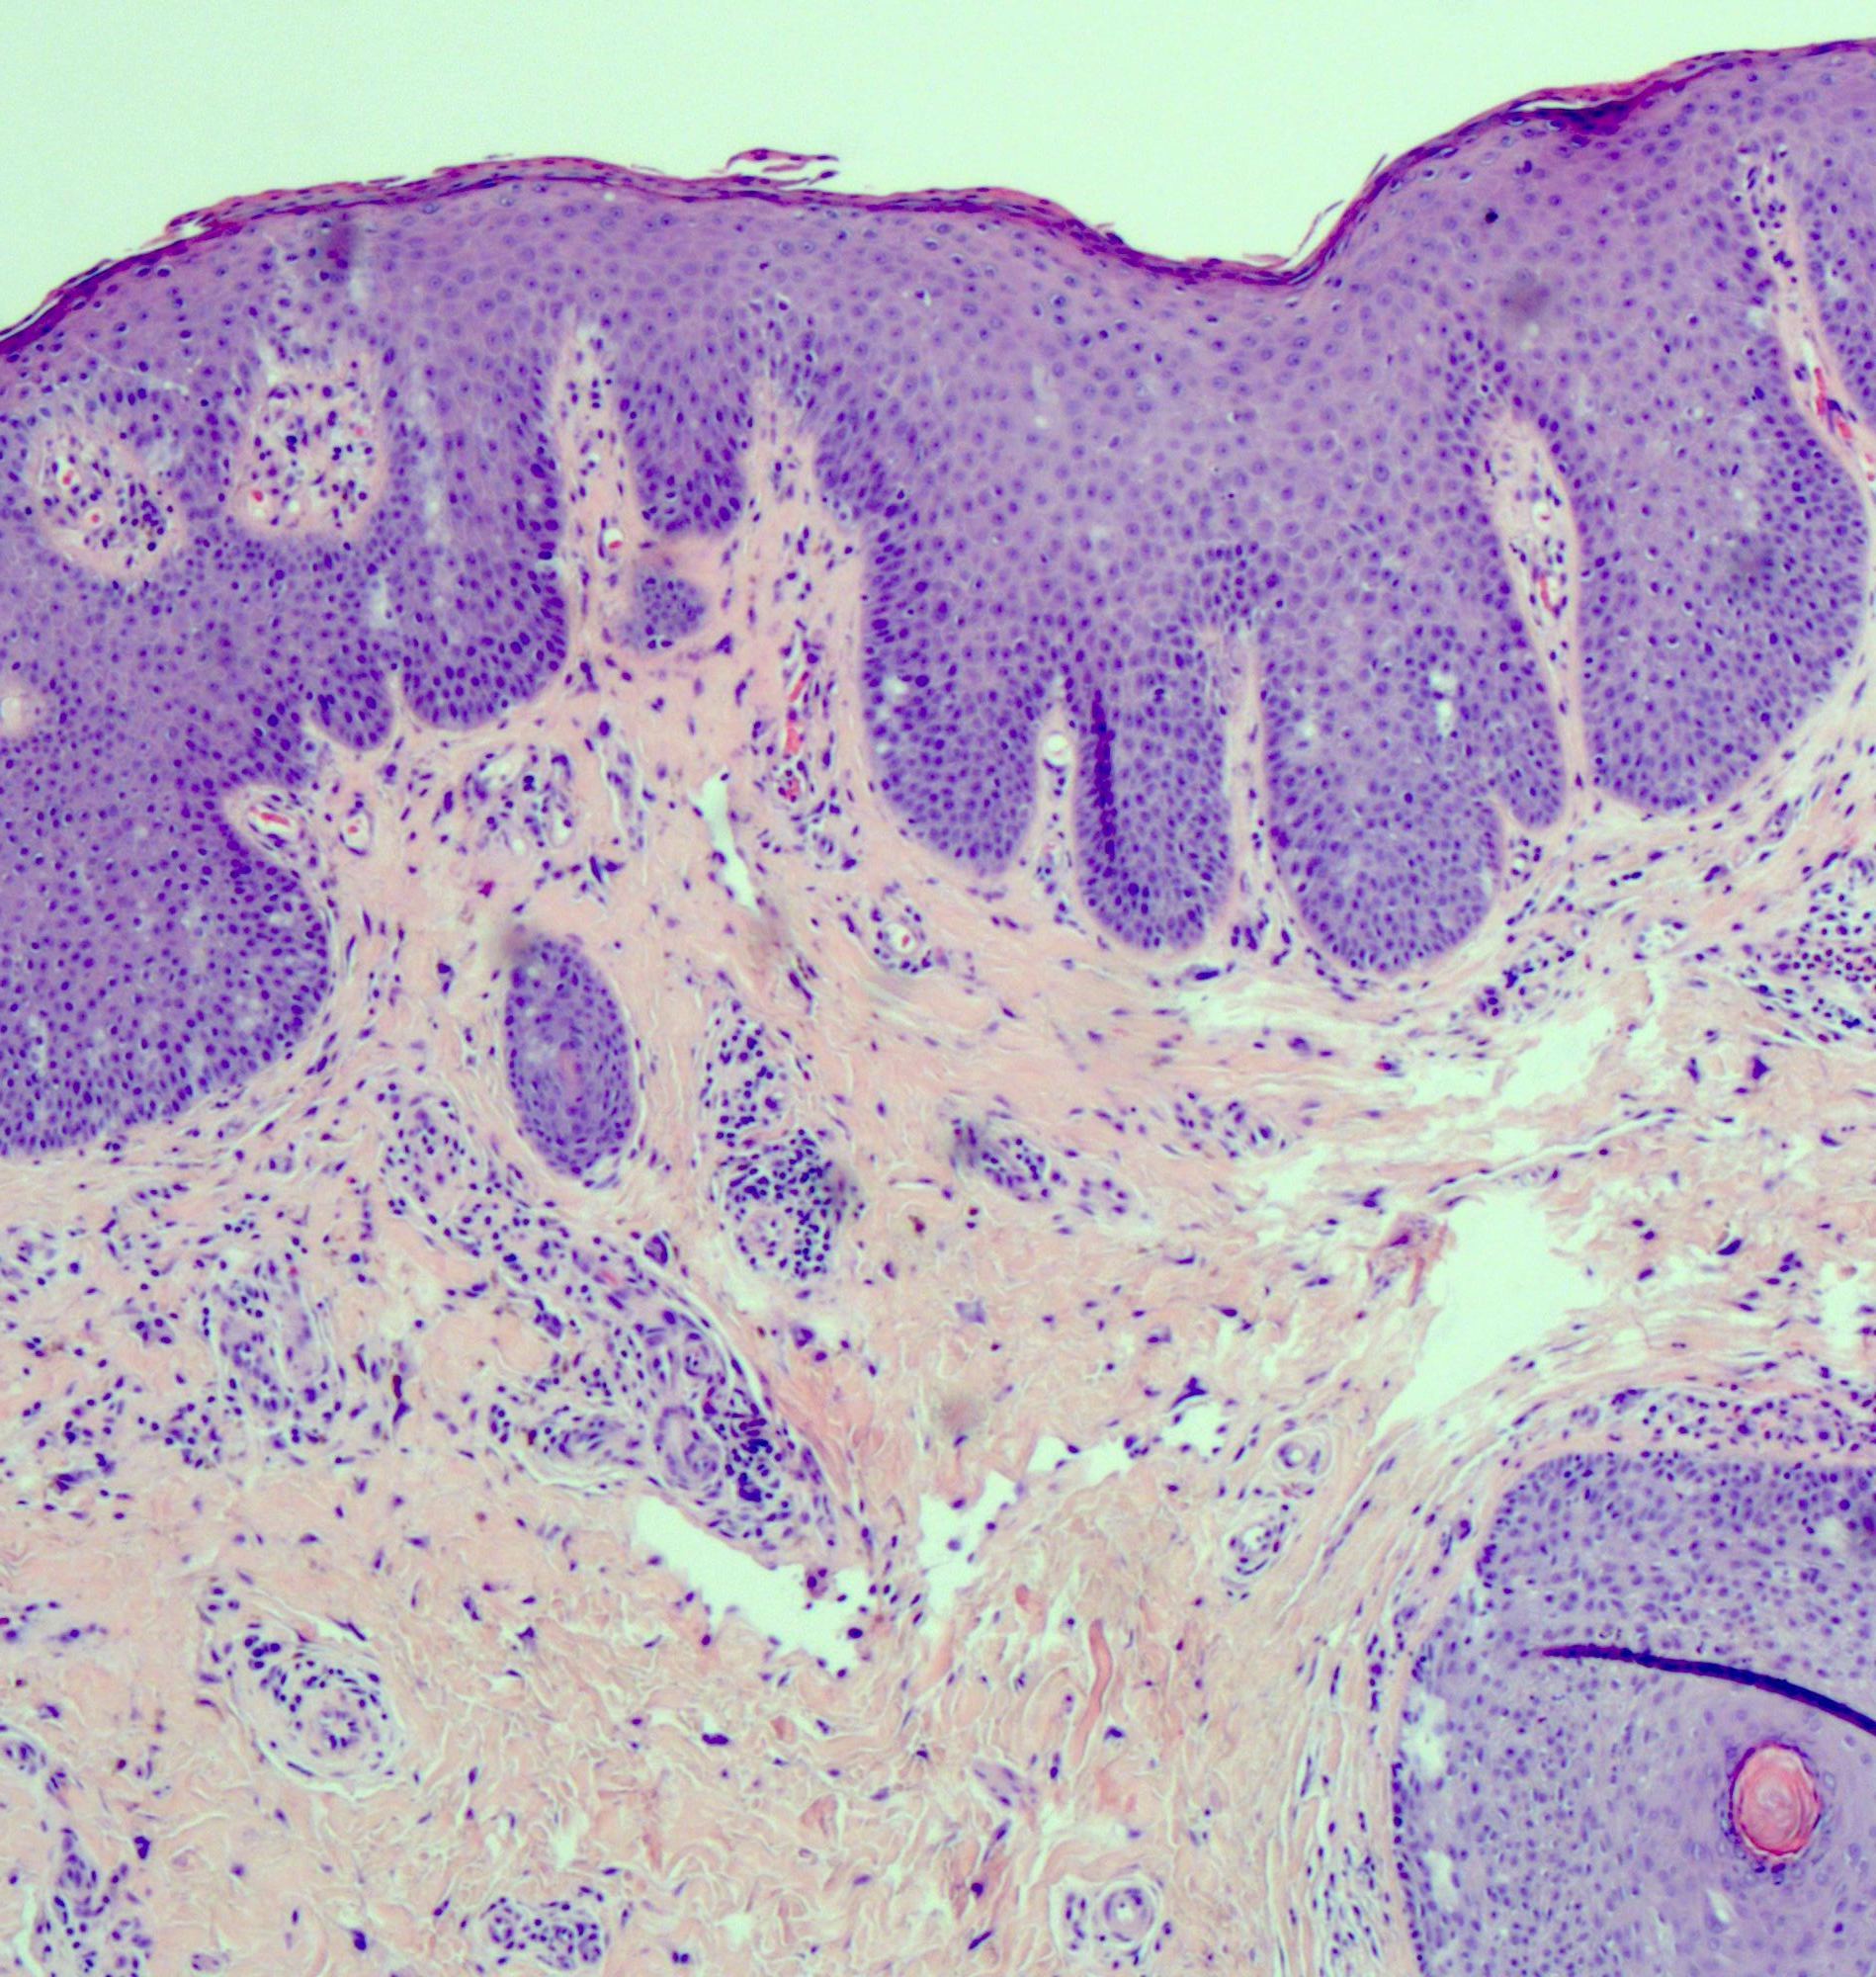

Differential diagnosis

- HPV independent vulvar intraepithelial neoplasia (VIN):

- Other terminology: differentiated VIN (dVIN), differentiated exophytic vulvar intraepithelial lesion (DEVIL), vulvar acanthosis with altered differentiation (VAAD), vulvar altered maturation (VAM)

- Shows epithelial hyperplasia and loss of normal maturation; often shows significant basal atypia and may show mutant pattern p53 immunostaining (Mod Pathol 2011;24:297)

- Lichen planus:

- Clinically, the presence of erosions, oral involvement, a burning sensation or a hyperkeratotic lesional margin favor a diagnosis of lichen planus over lichen sclerosus (Australas J Dermatol 2020;61:324)

- Typically involves mucosa or nonhair bearing skin

- Subepithelial band-like inflammatory infiltrate is directly under the squamous epithelium, without a separating area of fibrosis / sclerosis

- Pointed rete ridges are more common in lichen planus, while the presence of epidermal atrophy or basal lamina thickening favor lichen sclerosus (Am J Surg Pathol 1998;22:473)

- Early lesions of lichen sclerosus, before the fibrosis becomes established, can be difficult or impossible to distinguish from lichen planus; such cases can be signed out descriptively, indicating that follow up, with or without rebiopsy, should allow for definitive diagnosis

- Lichen planus can coexist with lichen sclerosus (J Low Genit Tract Dis 2017;21:204)

- Lichen simplex chronicus:

- Common; spares the vaginal mucosa (Dermatol Clin 2010;28:669)

- Epidermal hyperplasia is present, rather than atrophic changes, with no degenerative changes of the basal epithelial layer and no superficial subepidermal sclerosis

- Excoriation is common and may lead to subepidermal scarring but with variably sized collagen bundles and not the homogenized sclerotic band of lichen sclerosis

- Spongiosis / spongiotic dermatitis may be present but is not necessary for diagnosis (Int J Womens Dermatol 2017;3:58)

- Hypergranulosis is common